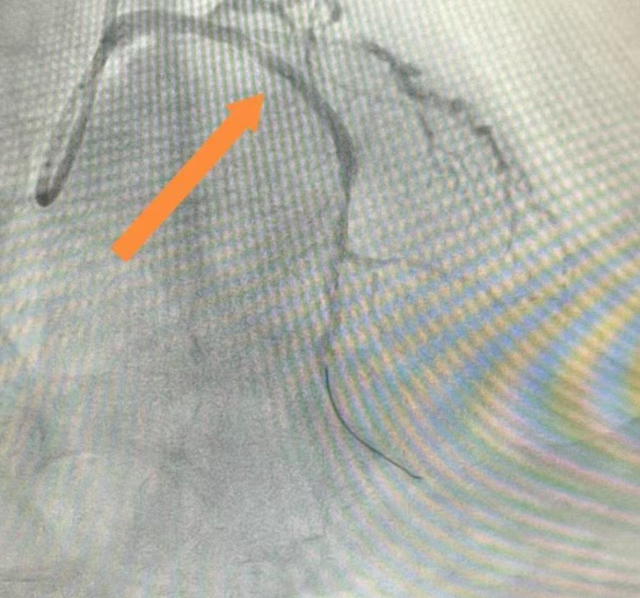

冠脉造影检查显示,于大爷心脏的重要血管——前降支近段完全闭塞,另外两处血管也存在严重狭窄。这意味着心肌供血严重受损,每一分钟延迟都会导致更多心肌细胞坏死。心脏康复科团队迅速为于大爷施行了急诊介入手术,成功在前降支近段植入支架,血流逐渐恢复,胸痛症状随之缓解。